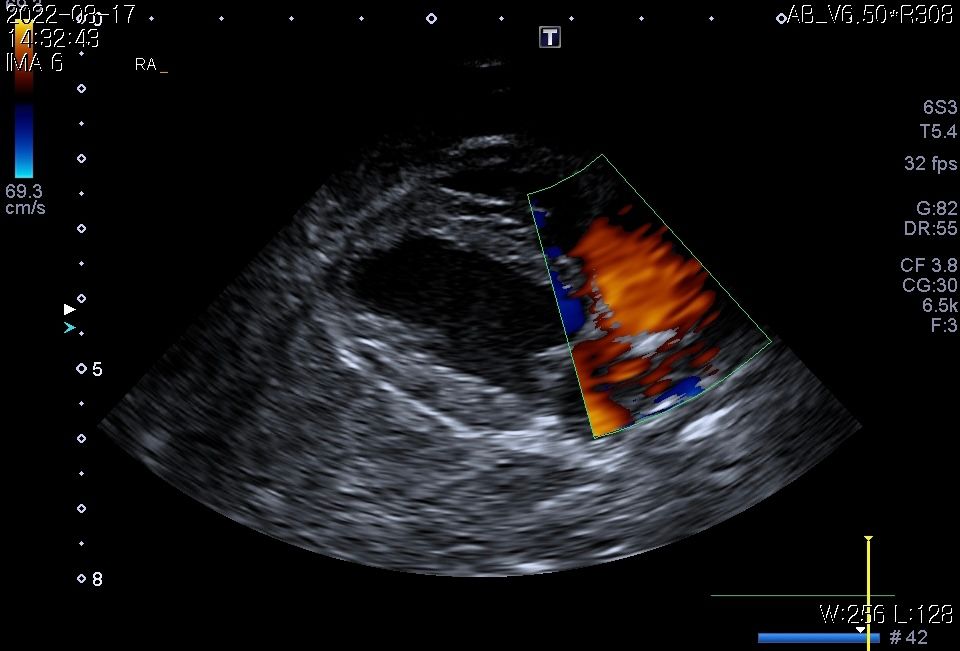

강아지 폐종양 의심되는데 봐주실 수있을까요?

11살강아지 입니다.

폐에 종양의심소견이 보인다고 해서요.

7월부터 기침을 간헐적으로 하다가 최근 심해져서 병원에 갔는데 엑스레이 상 폐종양이 의심된다고 해서요.

첨부해주신 사진만을 기초로 볼때 폐종양인 경우 좌측 폐전엽부의 종양이, 폐종양이 아닌 경우 종격동내의 종양 특히 흉선종양의 가능성이 높아 보입니다.